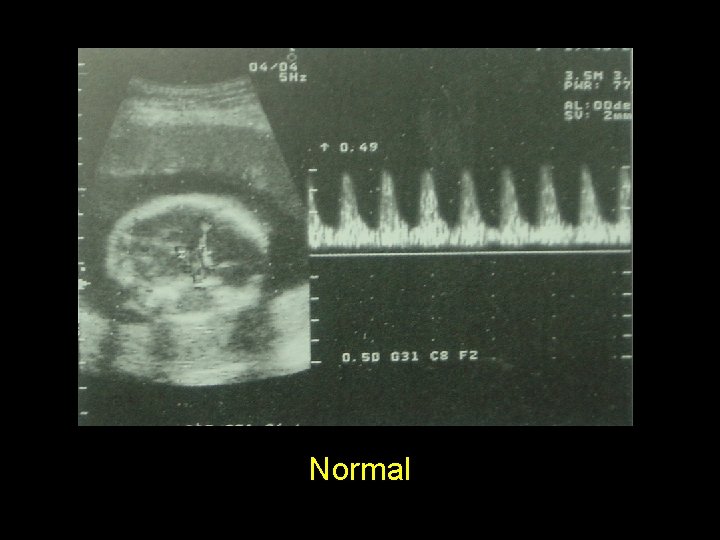

Systolic/Diastolic ratio = A/B Resistance index = A-B/A Pulsatility index = A-B/mean

Interpretation • Umbilical systolic-diastolic ratio (S/D ratio) • Ratio >3 at GA > 37 weeks = abnormal • More severe – Absent end-diastolic flow – Reversed end-diastolic flow UPI ↓ ������� ↓ ����� Diastolic↓

Normal